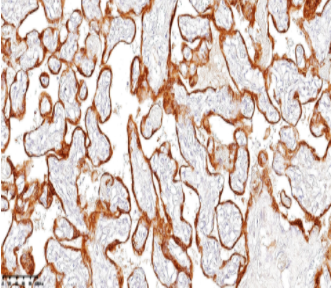

人胎盘催乳素(hPL)抗体 是一种特异性识别胎盘激素hPL(又称绒毛膜生长催乳素,HCS)的检测工具。hPL作为与人生长激素结构功能相似的肽类激素,通过调节母体代谢状态保障胎儿能量供应,其血清水平在妊娠第5周可检出,至34周达到峰值。该抗体能特异性标记绒毛膜癌中的合体滋养层细胞,在罕见睾丸滋养层肿瘤(类似子宫胎盘部位滋养细胞肿瘤)的诊断中具有独特价值——这类纯由中间型滋养细胞构成的肿瘤呈现hPL弥漫强阳性,而β-hCG仅局灶阳性。hPL抗体因此成为滋养层肿瘤病理分型和鉴别诊断的重要标志物。

阳性部位:

细胞质